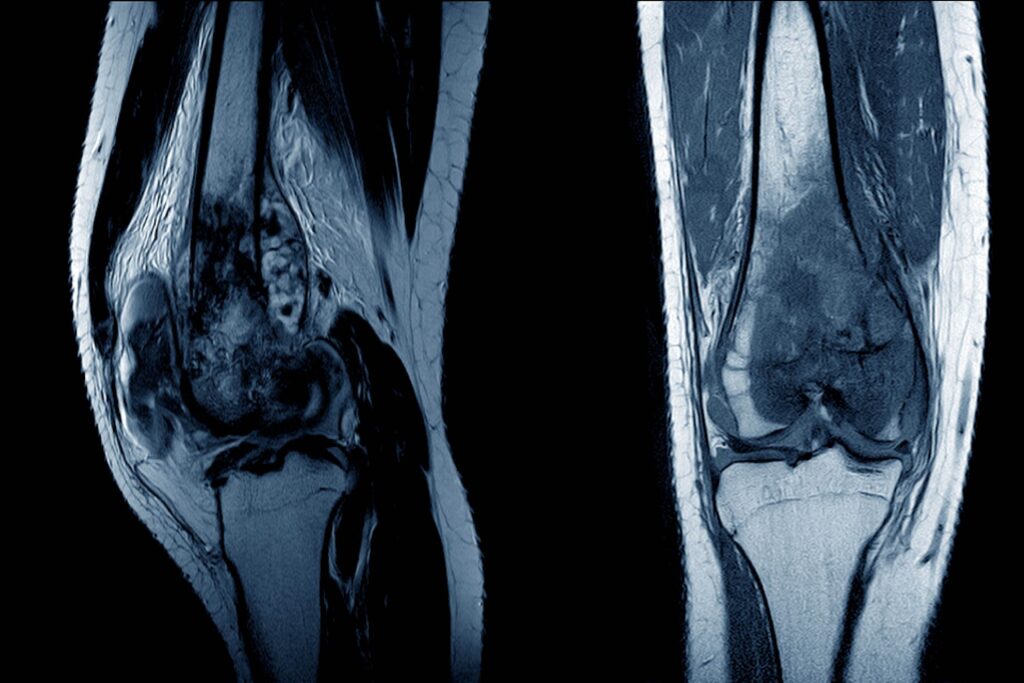

Leczenie Mięsaka kościopochodnego w Izraelu

Mięsak kościopochodny (osteosarcoma) jest agresywnym nowotworem wywodzącym się z tkanki kostnej, należącym do grupy mięsaków, czyli nowotworów rozwijających się z tkanek łącznych. Choroba charakteryzuje się szybkim wzrostem oraz skłonnością do tworzenia przerzutów, szczególnie do płuc, co stanowi główne wyzwanie terapeutyczne.

Współczesne leczenie osteosarcoma opiera się na podejściu wielodyscyplinarnym, łączącym chirurgię onkologiczną z intensywną chemioterapią wielolekową (m.in. metotreksat, doksorubicyna, cisplatyna), co pozostaje podstawą terapii i znacząco poprawiło przeżywalność pacjentów . Obecnie coraz większy nacisk kładzie się na leczenie oszczędzające kończynę, dzięki zaawansowanym technikom chirurgicznym oraz terapiom neoadiuwantowym, które umożliwiają zmniejszenie guza przed operacją.